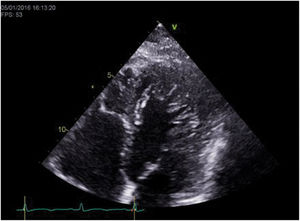

The transthoracic echocardiogram revealed LV myocardial hypertrabeculation with deep intertrabecular recesses communicating with the LV cavity as shown by color Doppler, meeting the LVNC diagnostic criteria of Jenni et al. (ratio of noncompacted to compacted layer thickness in end-systole in parasternal short-axis view: 2.5), Chin et al. (ratio of distance from the epicardium to the intertrabecular recess to the distance from the epicardium to the peak of the trabeculae in apical 4-chamber view: 0.3) and Stöllberger et al. (more than three trabeculae distal to the papillary muscles in apical 4-chamber view) (Figure 1). LV ejection fraction was 50%.

Cardiac MRI corroborated the echocardiographic findings, supporting the diagnosis of LVNC based on Petersen et al.’s criteria (ratio of noncompacted to compacted layer thickness in end-diastole: 4).